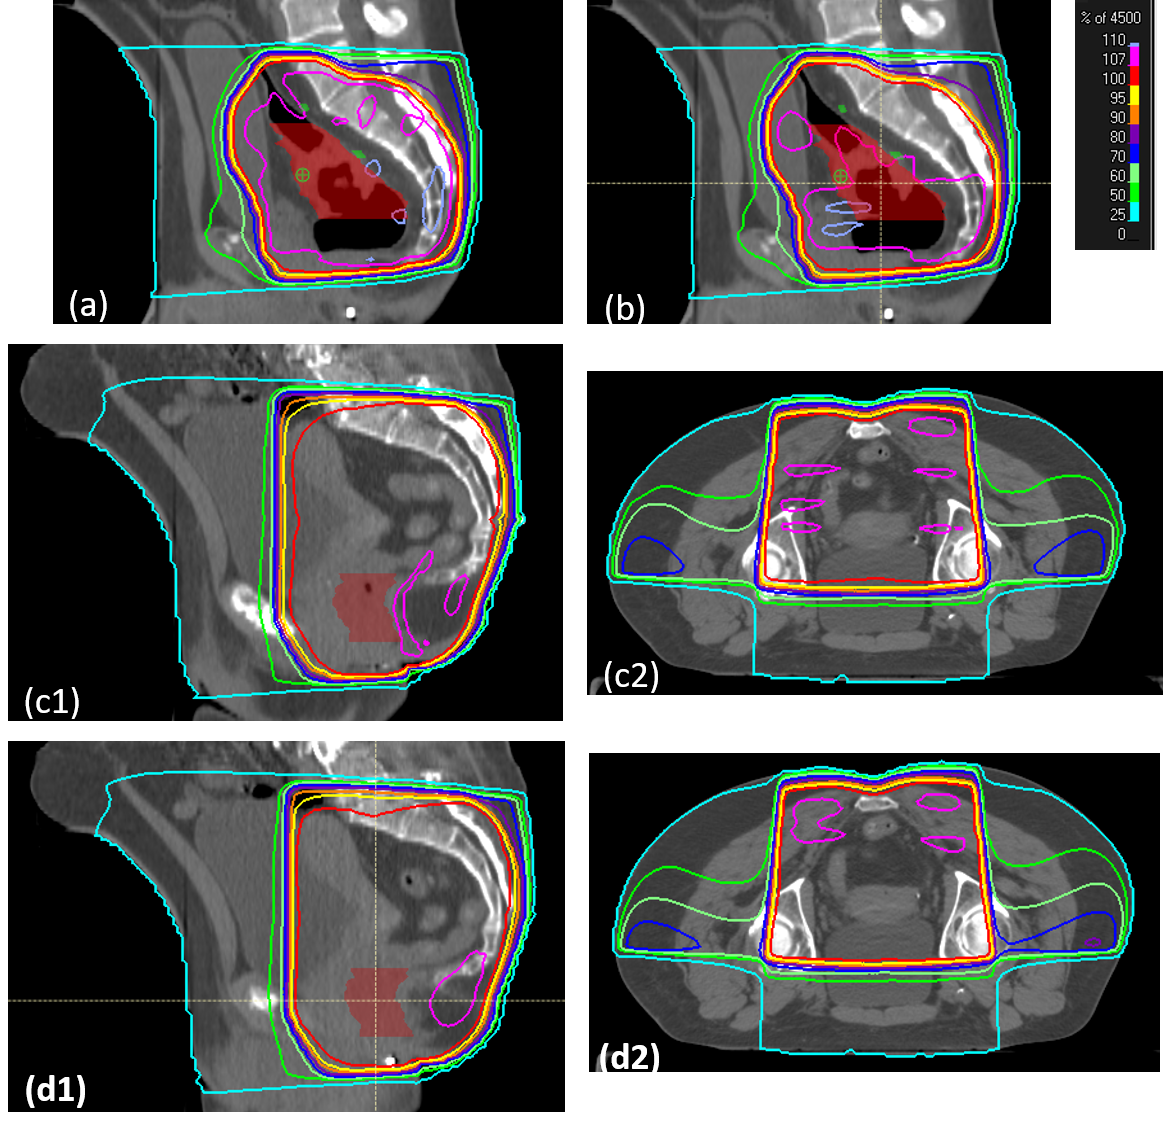

Refer to caption

Figure 6: The figure shows the boxplots of plans before and after field-in-field (FIF) for each configuration; (a) Volume exceeding 107% of Rx as a percentage volume of pseudo-region of interest (pROI) for different hotspot definitions, (b) Volume exceeding 107% of Rx as a percentage volume of pROI for different wedge settings, (c) For percentage hotspot dose of plans for different hotspot definitions, (d) For percentage hotspot dose of plans for different wedge settings. The plans scored as acceptable (\geq 4) are marked as blue and plans scored as unacceptable (\leq 3) are marked as red.

Figure 7: Plans with scores from 2 to 5: Part (a) scores 2 because of large 107% volume almost covering the entire planning target volume (PTV) area, part (b) scores 3 because the 107% hotspot was still large, but the plan could be improved by adding an additional subfield, part (c) scores 4 because there was too much 107% volume in the bowel region. Manually lowering the normalization would allow a score of 5. Parts (c1 and c2) are sagittal and transverse views of the same plan. Part (d) scores 5 with minimal hotspot located in the muscle region. Parts (d1 and d2) are sagittal and transverse views of the same plan.

In all the plans made by FIF, the average final hotspot dose percentage was reduced from 121% (σ𝜎\sigma = 14%) to 109% (σ𝜎\sigma = 5%). The hotspot dose percentage represents the maximum dose percentage in a plan formed by a fully connected volume with at least 8 cm3 in size. In other words, the dose percentage indicated by the hottest 8 cm3. Figure 6a,b shows the V107 as a percentage of pROI. As shown in Figure 6c,d, for plans with 45-degree wedge and 107% hotspot definition, FIF reduced average hotspot dose percentage from 117.6% (σ𝜎\sigma = 11.8%) to 108.7% (σ𝜎\sigma = 3.8%). For plans with 60-degree wedge and 107% hotspot definition, FIF reduced average hotspot dose percentage from 115.0% (σ𝜎\sigma = 16.9%) to 108.9% (σ𝜎\sigma = 5.5%). For plans with no wedge and 107% hotspot definition, FIF reduced average hotspot dose percentage from 134.2% (σ𝜎\sigma = 5.7%) to 110.2% (σ𝜎\sigma = 3.5%).For plans with 45-degree wedge and 106% hotspot definition, FIF reduced average hotspot dose percentage from 117.6% (σ𝜎\sigma = 11.8%) to 108.8% (σ𝜎\sigma = 7.4%).

Regardless of the settings, for all the acceptable plans,the 107% hotspot volume after FIF comprised less than 20% volume of pROI (Figure 6a,b) or 500 cm3𝑐superscript𝑚3cm^{3}. Figure 6c,d shows that none of the plans with more than 110% hotspot dose percentage after FIF was considered clinically acceptable. For the non-wedged plans, the average number of subfields was 5.9, and the average maximum hotspot percentage was 110.2%. This indicated that the hotspots on some of the non-wedged plans can be further reduced by increasing the maximum number of subfields allowed. For all the plans evaluated, the plans scored as 4 could be rated as 5 after reduction of the normalization to the 100% isodose line covering 98% of PTV instead of 99% of PTV. Examples of plans with different scores and the reason for the score are shown in Figure 7.